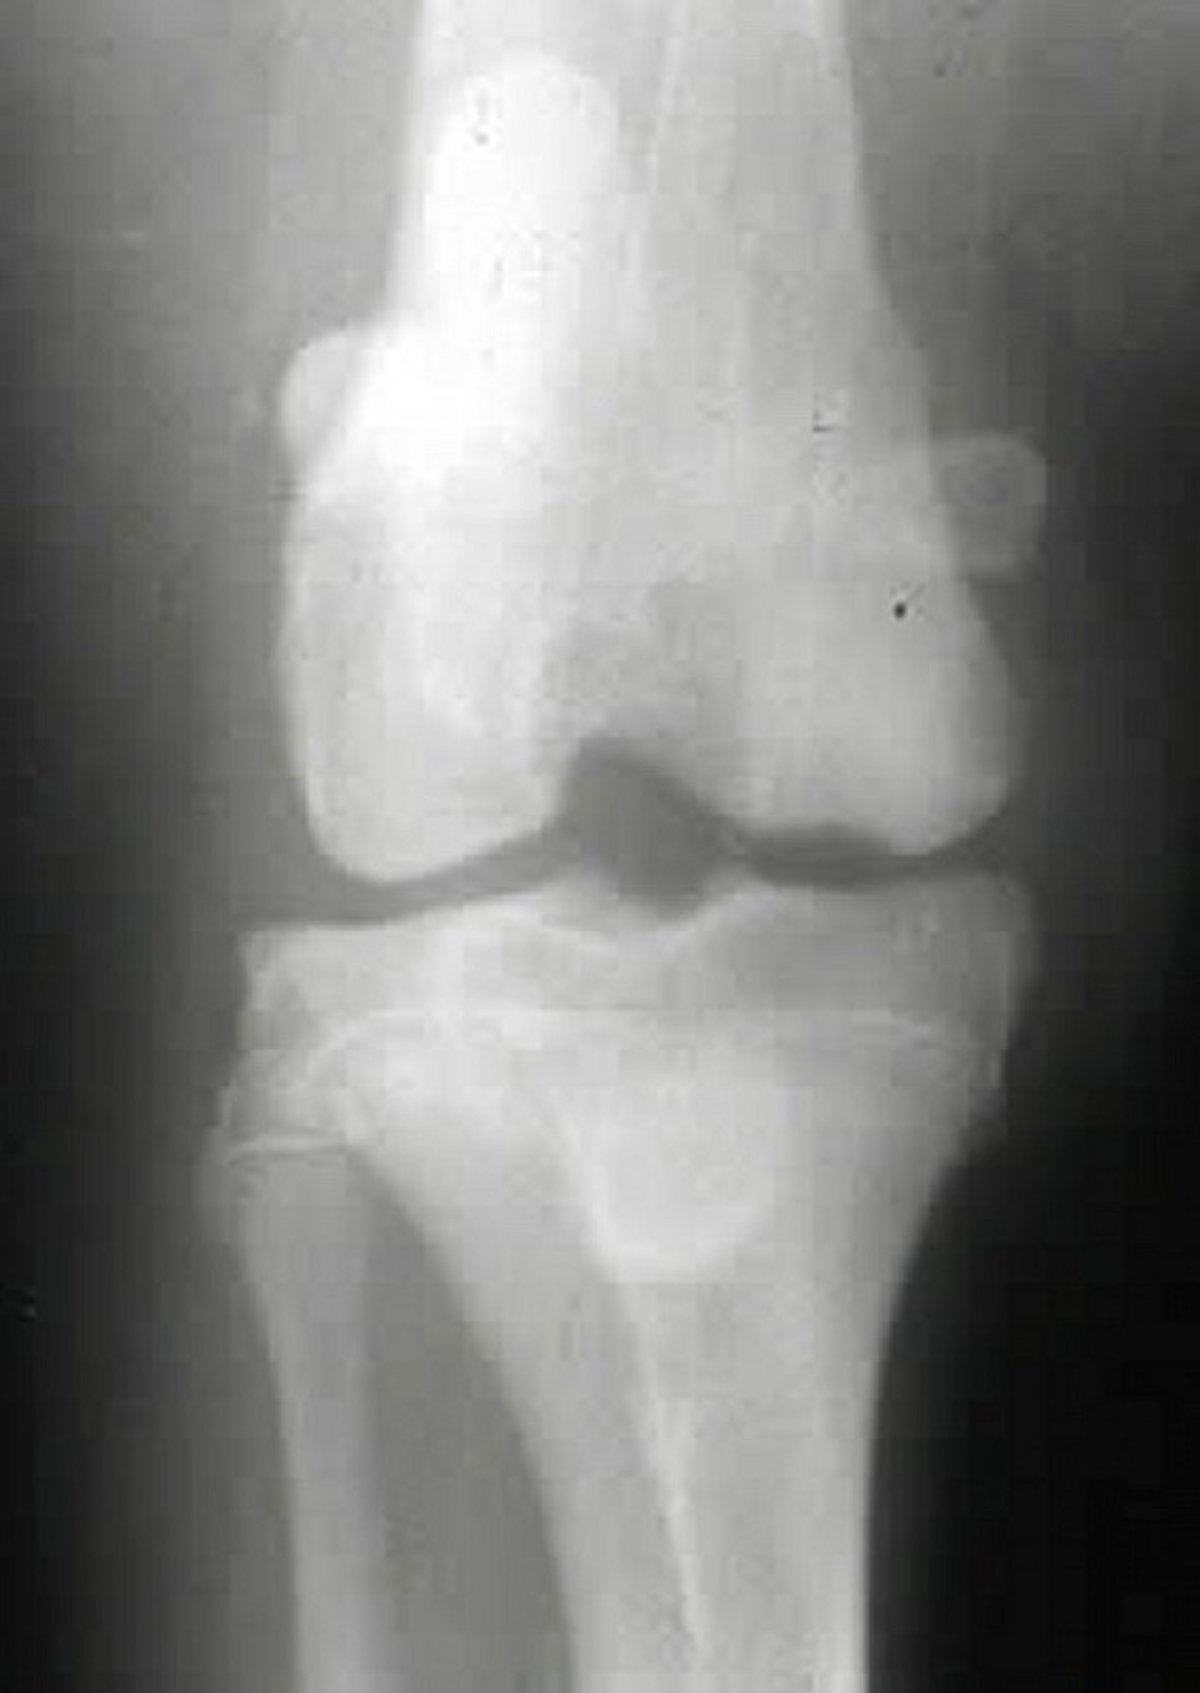

Craniocaudal radiographic view of the right stifle joint in a dog with osteochondrosis. Note the subchondral flattening of the medial femoral condyle.

Courtesy of Dr. Ronald Green.